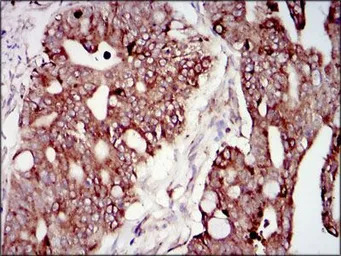

IHC-P analysis of rectum cancer tissue using GTX60633 PI3 kinase p85 alpha antibody [6G10].

IHC-P analysis of cervical cancer tissue using GTX60633 PI3 kinase p85 alpha antibody [6G10].